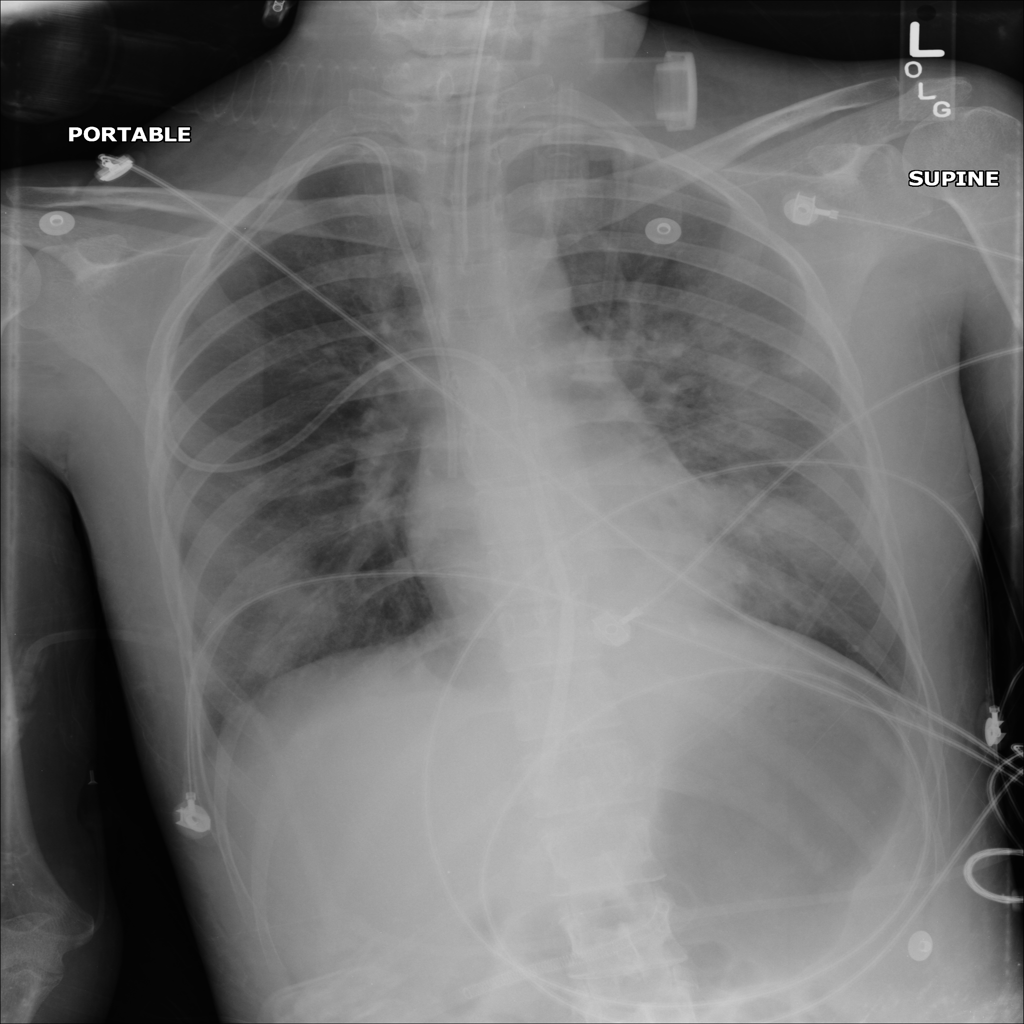

Showing up to 90 reference images for Pneumonia.

PAT-B3C3 · IMG-001Pneumonia

PAT-B3C3 · IMG-001

PA